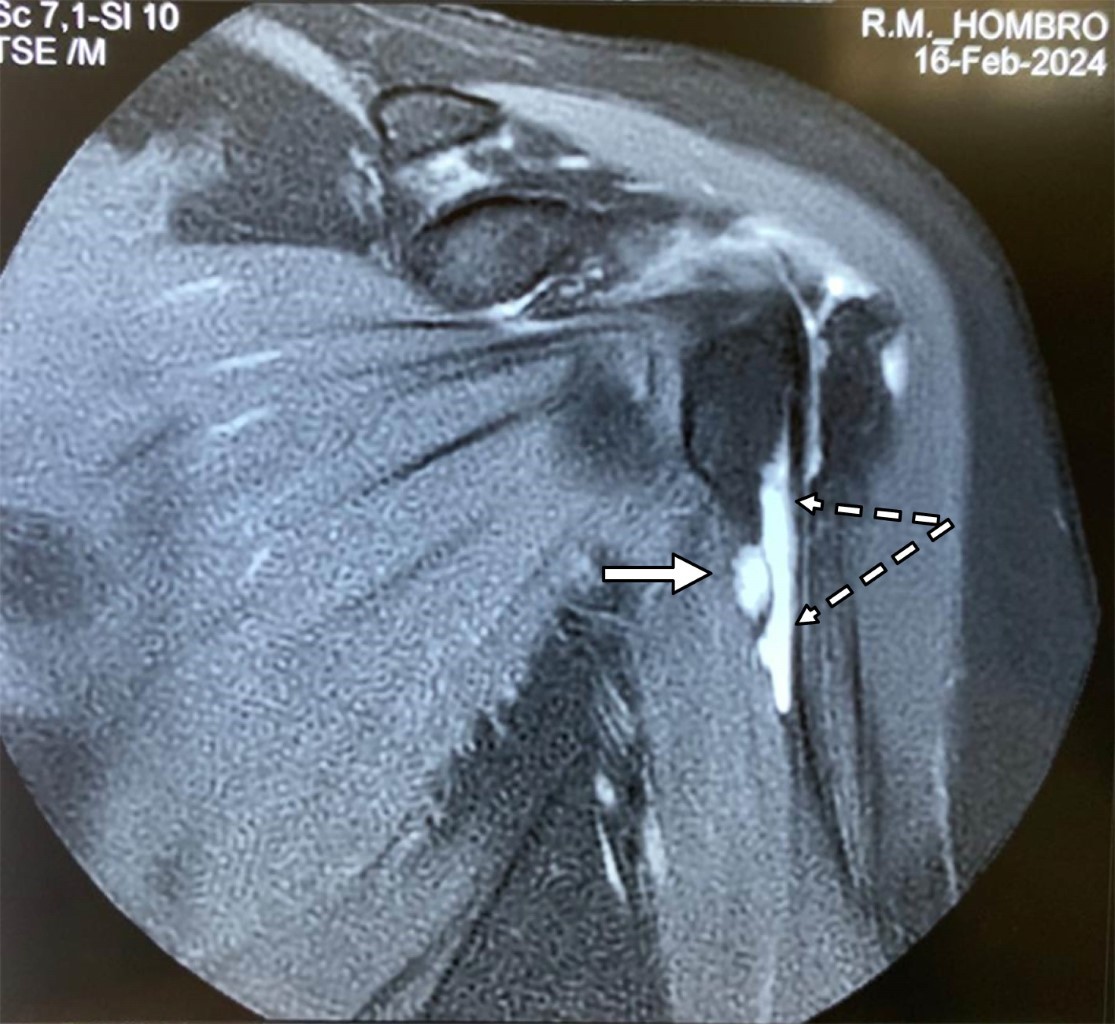

Se trata de paciente femenino de 69 con dolor en el hombro izquierdo de seis meses de evolución, principalmente con movimientos de abducción y flexión de codo. A la exploración de hombro izquierdo: arcos de movimiento limitados en abducción a 90° por dolor al igual que rotación externa de 45°, a la palpación masa dolorosa de aproximadamente 2 cm en borde interno del tendón de la porción larga del bíceps por debajo de la corredera bicipital. Prueba de choque de Neer, Hawkins y prueba de Yergason positivas; pruebas de inestabilidad de la articulación glenohumeral negativas. Las radiografías simples no mostraron hallazgos anormales. La resonancia magnética mostró: tendinosis del supraespinoso con ruptura parcial en su inserción, además de acromion tipo III con osteofitos subacromiales causantes de pinzamiento (Figura 1); en ponderación T2 se encontró tendinopatía de la porción larga del bíceps braquial con incremento de líquido en la corredera bicipital y quiste sinovial en su tercio proximal de 2.0 × 1.4 × 1.2 cm, con apariencia de estar encapsulada por la vaina del tendón bicipital (Figuras 2 y 3). Se canalizó a cirugía articular.

Figura 2